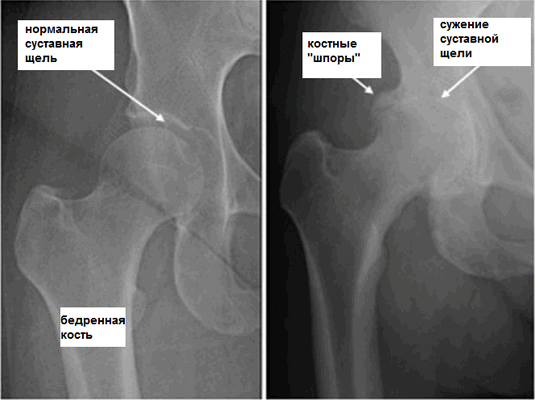

Для каждой стадии характерна своя симптоматика, выраженность которой зависит от степени сужения суставной щели, количества образовавшихся костных наростов.

| Степень тяжести коксартроза | Характерные симптомы и рентгенографические признаки |

| Первая | Суставная щель сужена неравномерно, вокруг вертлужной впадины сформировались единичные остеофиты. Возникают слабые дискомфортные ощущения, но чаще заболевание клинически не проявляется |

| Вторая | Суставная щель сужена почти в 2 раза, головка бедренной кости смещена, деформирована, увеличена, а костные наросты обнаруживаются даже за пределами хрящевой губы. Боли в бедре становятся постоянными, сопровождаются значительным ограничением подвижности |

| Третья | Полное или частичное сращение суставной щели, множественные костные разрастания, расширение головки бедренной кости. Боли возникают днем и ночью, распространяются на бедра, голени. Передвижение возможно только с помощью трости или костылей |

Рентгенологическое исследование

Стадия коксартроза устанавливается проведением рентгенографического исследования. На полученных изображениях отчетливо просматриваются деструктивные изменения в тазобедренном суставе. Это сужение суставной щели, деформация костных поверхностей, формирование остеофитов.